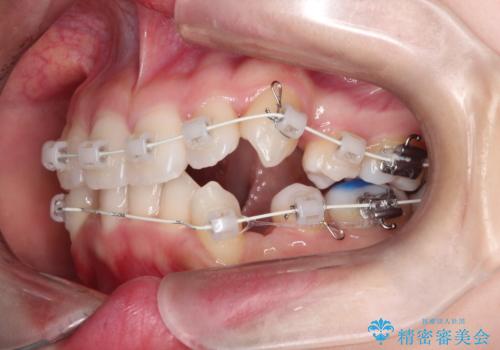

- 矯正装置

- 審美装置

- 左上の犬歯の凸凹や正中のずれを主訴に来院されました。

凸凹を治すために、上下左右の小臼歯を抜歯してワイヤー矯正を行いました。

患者様には、顎間ゴムを使用していただくことで、2年という期間で治療を終了することができました。